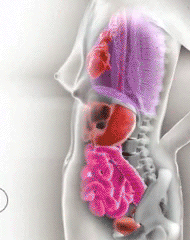

5.怀孕后,妈妈们的身体变化!